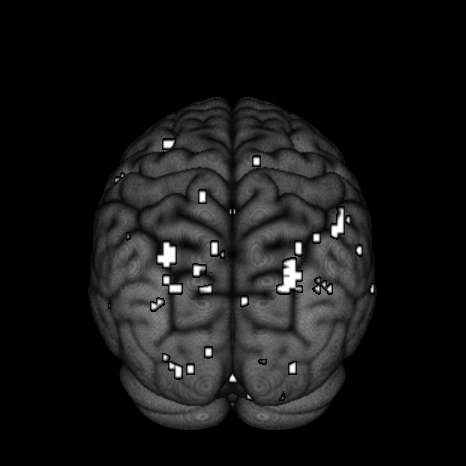

Finally, we look at the effect of fame using thresholded PPMs. The activation threshold is set to of the global mean value, and the probability threshold is set to . Figure 9 shows the activation regions projected onto the pial surface. We can see that there is a match in terms of a majority of activation regions inferred from SVARO and PMCMC. A closer look reveals that PMCMC tends to make more scattered predictions across the posterior regions of the brain. The number of activation regions from PVB are far greater than the number obtained from the other two approaches, and are more widely dispersed across the brain. From our simulation study results, we suspect that these scattered activated regions are likely false positives.